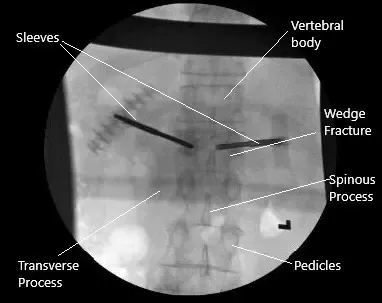

Radiografía intraoperatoria de la cifoplastia.

Se introdujo el C-arm y la vértebra L1 se localizó en la vista de la PA y lateral. Los pedículos de las vértebras L1 estaban localizados en ambos lados. Se utilizaba una aguja espinal para hacer una entrada a través de la articulación facetaria en el pedículo. Se hicieron entradas bilaterales en los pediculos laterales.

Una vez que las agujas de Jamshidi estaban en el pedículo medial, se revisó la vista lateral y se encontró que estaban en una posición satisfactoria. Las agujas Jamshidi avanzaron aún más. Se realizó una biopsia ósea de las vértebras mediales y la envió a histopatología.

Una vez que encontramos las agujas Jamshidi en su posición adecuada, se retiraron las agujas Jamshidi. Las mangas se retiraban aproximadamente un centímetro y se insertaban globos a ambos lados. Los globos estaban inflados. Sentimos que había una brecha en la placa inferior del lado derecho, así que la inflación se detuvo en ese momento.